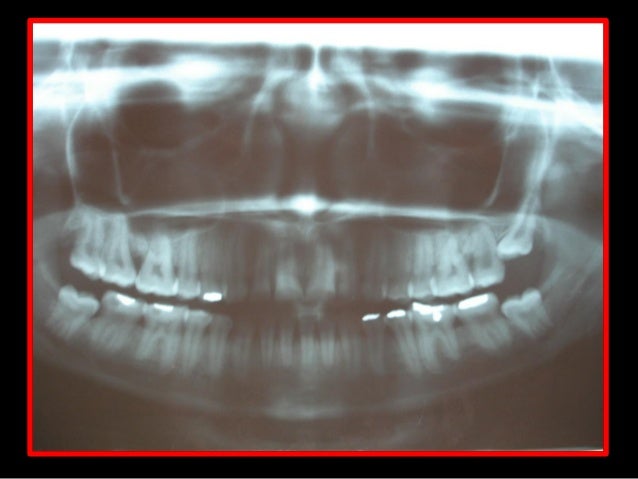

29. 29. Radiografia Periapical Início do Tratamento Após 11 meses de Tratamento

Em uma oclusão fisiológica ou orgânica, no final do fechamento mandibular, a ação dos músculos elevadores promove o assentamento dos côndilos nas fossas mandibulares do osso temporal, denominado posição de relação cêntrica (RC), coincidente com o máximo de contatos dentários posteriores bilateral, denominado máxima intercuspidação (MI) ou oclusão dentária. Como resultado a mandíbula assume posição estável denominada oclusão em relação cêntrica (ORC), na dimensão vertical de oclusão (DVO). Em seguida o relaxamento dos músculos elevadores gera a dimensão vertical de repouso (DVR).